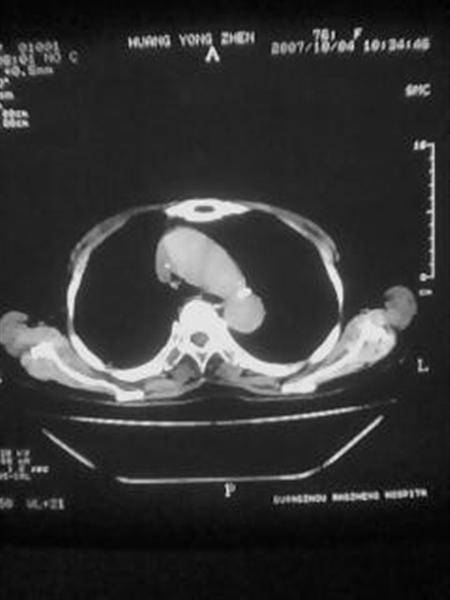

考虑肺癌胸膜转移可能性大。

考虑肺癌,肺、胸膜转移可能性大.

怎么没有病史呢?支持:考虑肺癌,肺、胸膜转移可能性大.

右下肺周围型肺癌伴双肺右侧叶间 胸膜及右肺门淋巴结转移